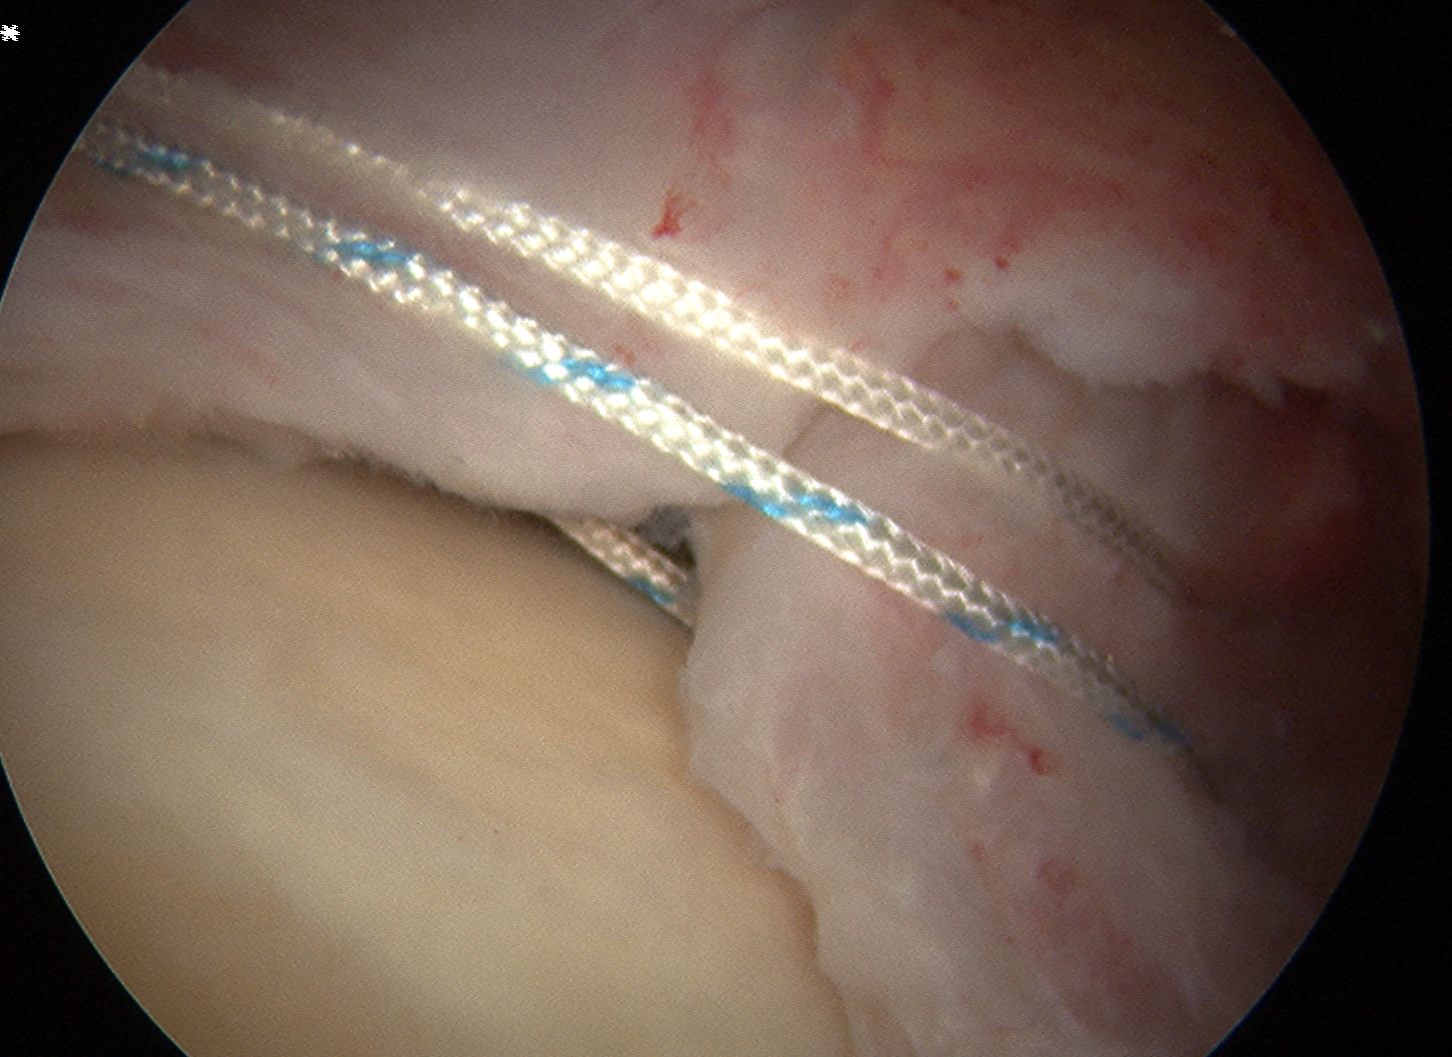

D. Transosseous equivalent / suture bridge

Technique

- biomechanically replicate tradional open transosseous

- sutures crossed as below in double row

- aiming to increase contact between cuff and footprint